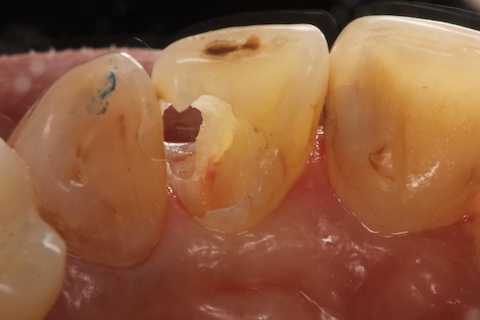

40代女性、右上2、自発痛-

かなりひどい虫歯で、外側表面のエナメル質はなんとか残したが、ペラペラだ。

スプーンエキスカベータで軟化象牙質を剥がすと簡単に露髄した(黄色矢印)。